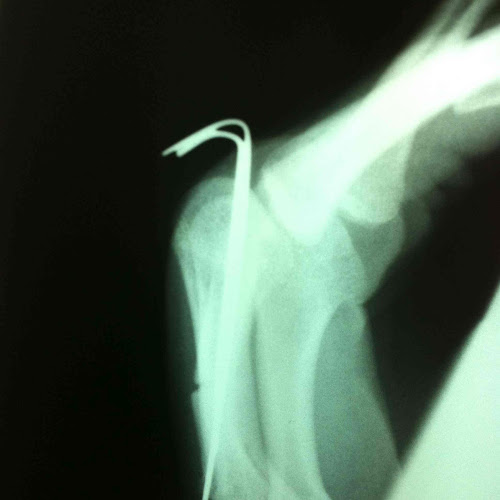

5th metacarpal fracture

when life breaks you, come back stronger as wolverine